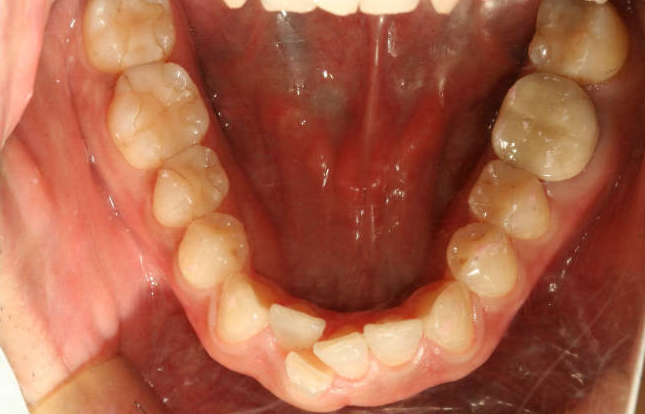

이분은 아래 앞니가 하나 완전히 겹쳐서 나있으신데요

하악전치를 한개만 뽑기도 하지만

그렇게 할경우에 교합을 맞추기가 매우 어렵습니다.(아래 앞니가 홀수개가 되면서 뒤에 어금니의 사이사이로 물리게 만들기 어렵습니다)

이 경우에는 여러가지 방법을 이용해서 비발치교정이 가능합니다